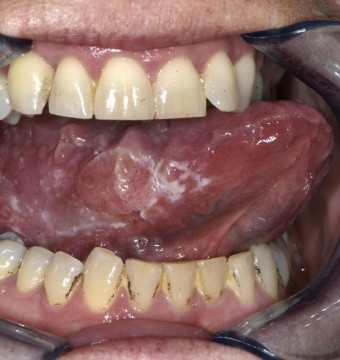

Bij lichamelijk onderzoek zagen wij een reticulair netwerk van witte lijnen op beide zijden van de tong. Dit zijn de zogenaamde wickhamstriae die typerend zijn voor lichen planus. Maar wat ons nog meer opviel, was dat er in dat netwerk een lenticulaire papel zichtbaar en voelbaar was, die drukpijnlijk was bij palpatie. Wat is uw diagnose?